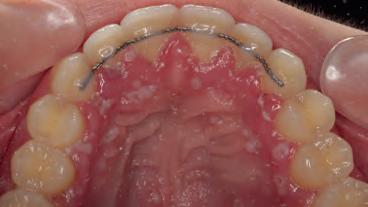

We zien een heftig ontstoken gingiva met talrijke blaasjes; deze gaan gemakkelijk stuk en resulteren in pijnlijke, aftachtige ulceraties. Herpesachtige ulceraties komen voor op het palatum, gingiva en de wang (afbeelding 1.1-1.5).

Occlusaal aanzicht bovenkaak